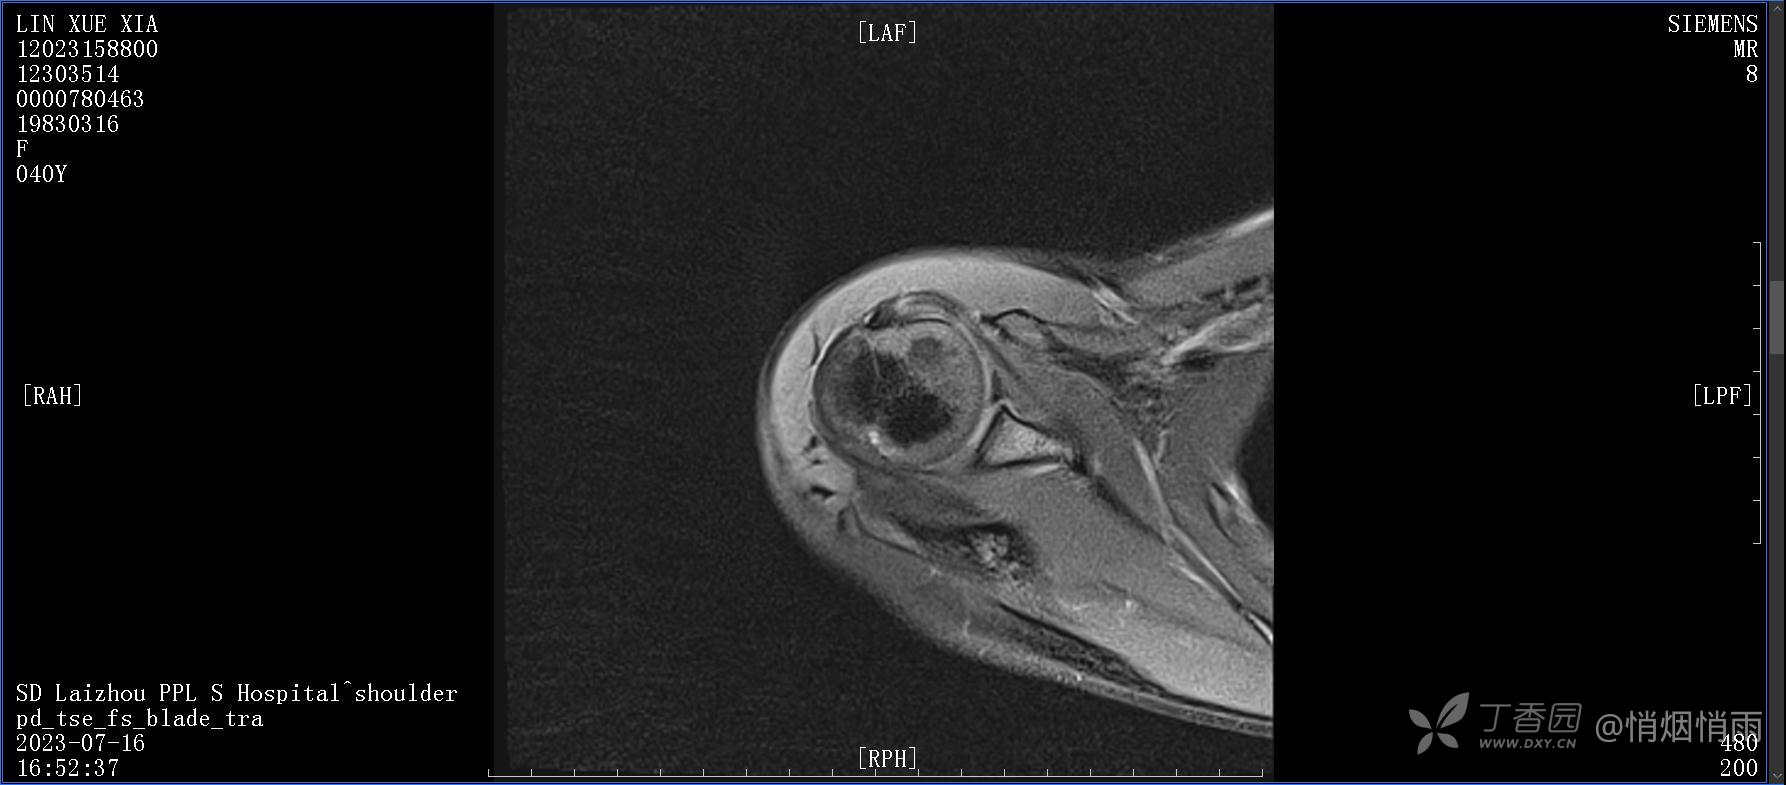

查体:右肩关节局部轻度肿胀,肩胛区压痛明显,痛处不固定,肩关节痛性活动受限,jobe test(+),lift -off test(+),中指、环指感觉较余指减退,余肢端感觉及血运情况可。

目前的诊断,暂时依据辅助检查诊为肩袖损伤,但是患者疼痛的性质和特点,却不是单纯的肩袖损伤所致。考虑过胸廓出口综合征,但是该疾病会出现肩胛区的疼痛吗?(由于考虑到费用的问题,没再进行下一步的检查)带状疱疹会有如此的症状吗?